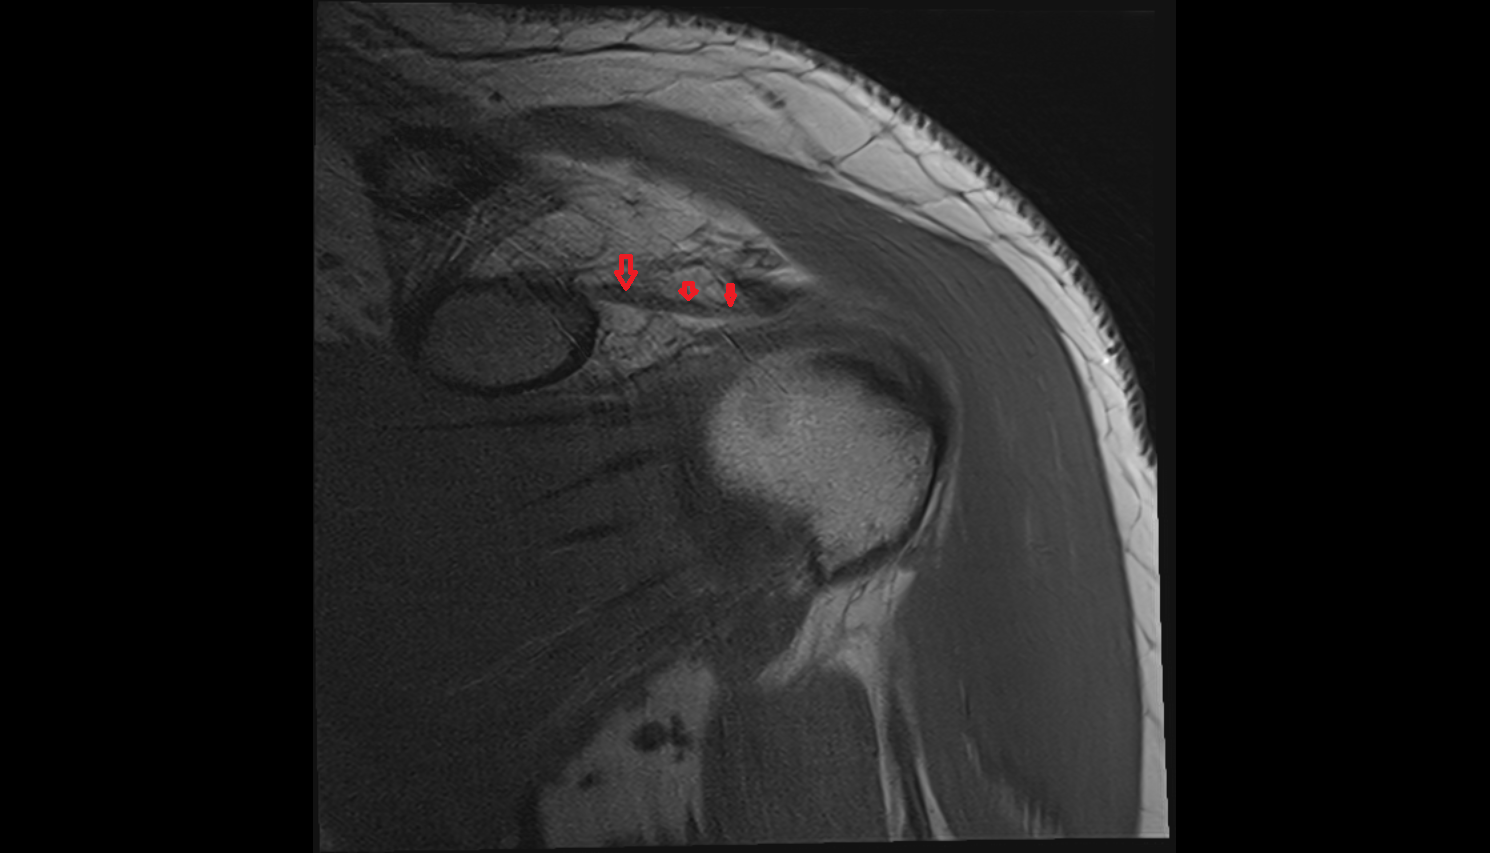

- Articular disc of temporomandibular joint

- Anterior Band of Articular Disc TMJ

- Posterior band of articular disc, TMJ

- Intermediate zone of articular disc

- Superior retrodiscal layer

- Attachment of superior head of lateral pterygoid muscle

- Attachment of inferior head of lateral pterygoid muscle